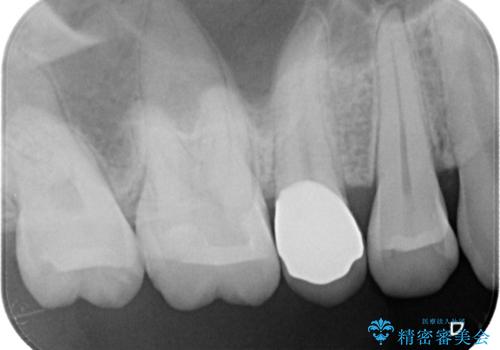

- 定期検診にて虫歯を発見したため、セラミッククラウン、セラミックインレーにて治療を行いました。

小臼歯の虫歯は歯髄に近かったため、部分的断髄法にて歯髄を部分的に保存した治療をおこなっています。